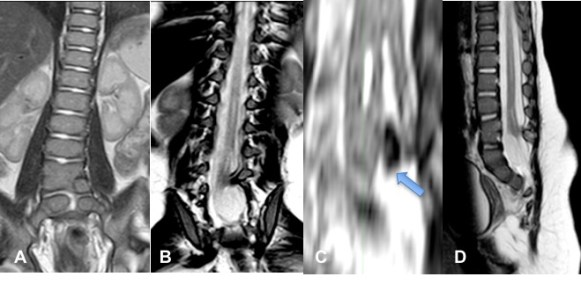

il s’agit d’une malformation rachis-médullaire complexe avec une moelle séparée en deux par un éperon central. la diastématomyélie associe donc des anomalies médullaires et des anomalies vertébrales. la malformation provoque une traction sur la moelle épinière qui entraine une paralysie progressive.

Il en résulte la présence d’un éperon osseux (type 1), contenant souvent une artériole, ou d’une bride fibreuse (type 2) qui divise la moelle, la fixe aux plans ostéo-duraux, et exerce un effet de traction (moelle attachée).

il existe souvent de plus des anomalies de fusion vertébrales et des hémivertèbres.